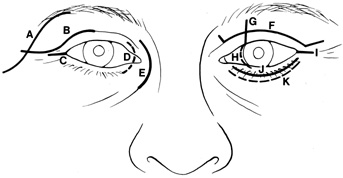

LATERAL ORBITOTOMY Lateral orbitotomy originally was popularized by Kronlein8 in 1888. The incision described by Kronlein was a reverse C-shaped incision

placed over the lateral rim and extending superiorly toward the

hairline and inferiorly toward the ear. This resulted in an unsightly

scar and a high likelihood of damage to the seventh cranial nerve. Subsequently, a

number of superior skin incisions have been devised to allow

exposure of the bony lateral orbital wall and access to the lateral

retrobulbar space.9–11 Currently, the lateral wall is most often approached through either a

canthotomy incision (modified Berke),12 or an upper eyelid crease incision extending into a lateral “laugh

line.”13 Rarely, a coronal incision in the hairline with subgaleal dissection of

close postoperative monitoring of vision. EYELID CREASE LATERAL ORBITOTOMY This approach affords excellent exposure of the lateral orbital rim through

an incision placed within the upper eyelid crease, which may extended

laterally into a temporal “laugh line” (Fig. 6). Infiltration with local anesthetic with epinephrine (1:200,000) at

CANTHOTOMY APPROACH Many deep orbital lesions requiring removal of the lateral orbital rim

can be approached through a smaller lateral canthotomy incision. Although

Berke17 initially described a fairly extensive lateral canthal incision extending

back over the zygomatic arch for 5 to 7 cm, this longer incision often

leaves an unsightly scar and may risk damage to the seventh cranial

nerve. Because of the extensibility of the periocular tissues, exposure

of the lateral orbital rim usually can be accomplished through a

small lateral canthotomy incision measuring 1 to 1.5 cm in length (Figs. 10, 11, and 12). With wide undermining in the suborbicularis plane and retraction